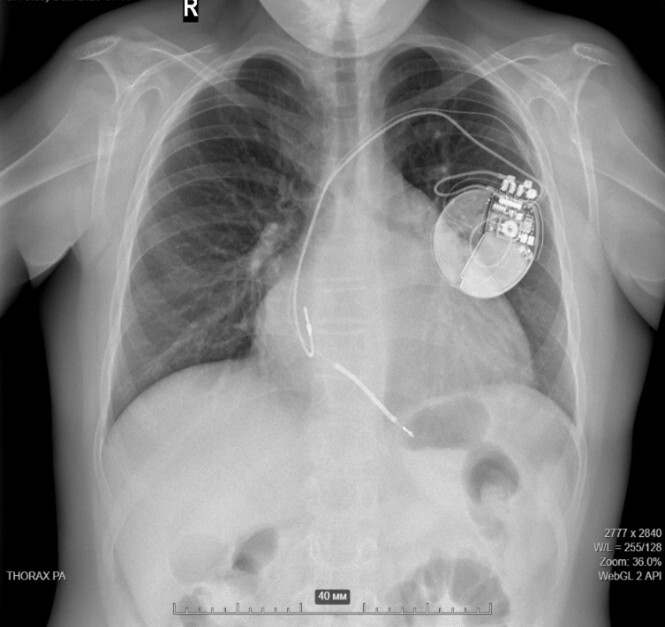

Ребенок с имплантированным ИКД.

Разряд ИКД купирует пароксизм фибрилляции желудочков.